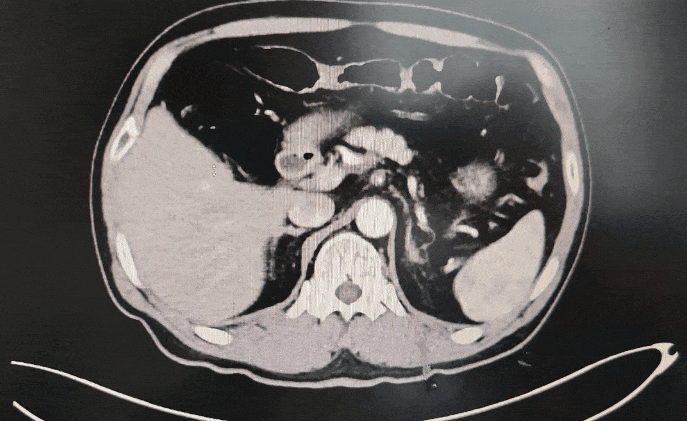

◈ 2022-8-10 胸腹盆增强CT提示:胰腺体部强化减低并胰管局限性稍扩张,肠系膜上动脉、腹腔干近段及局部分支软组织影包绕,考虑患者胰腺占位诊断明确(占位大小无法准确评估),但需鉴别恶性肿瘤及免疫相关疾病。

2022-8-10 胸腹盆增强CT